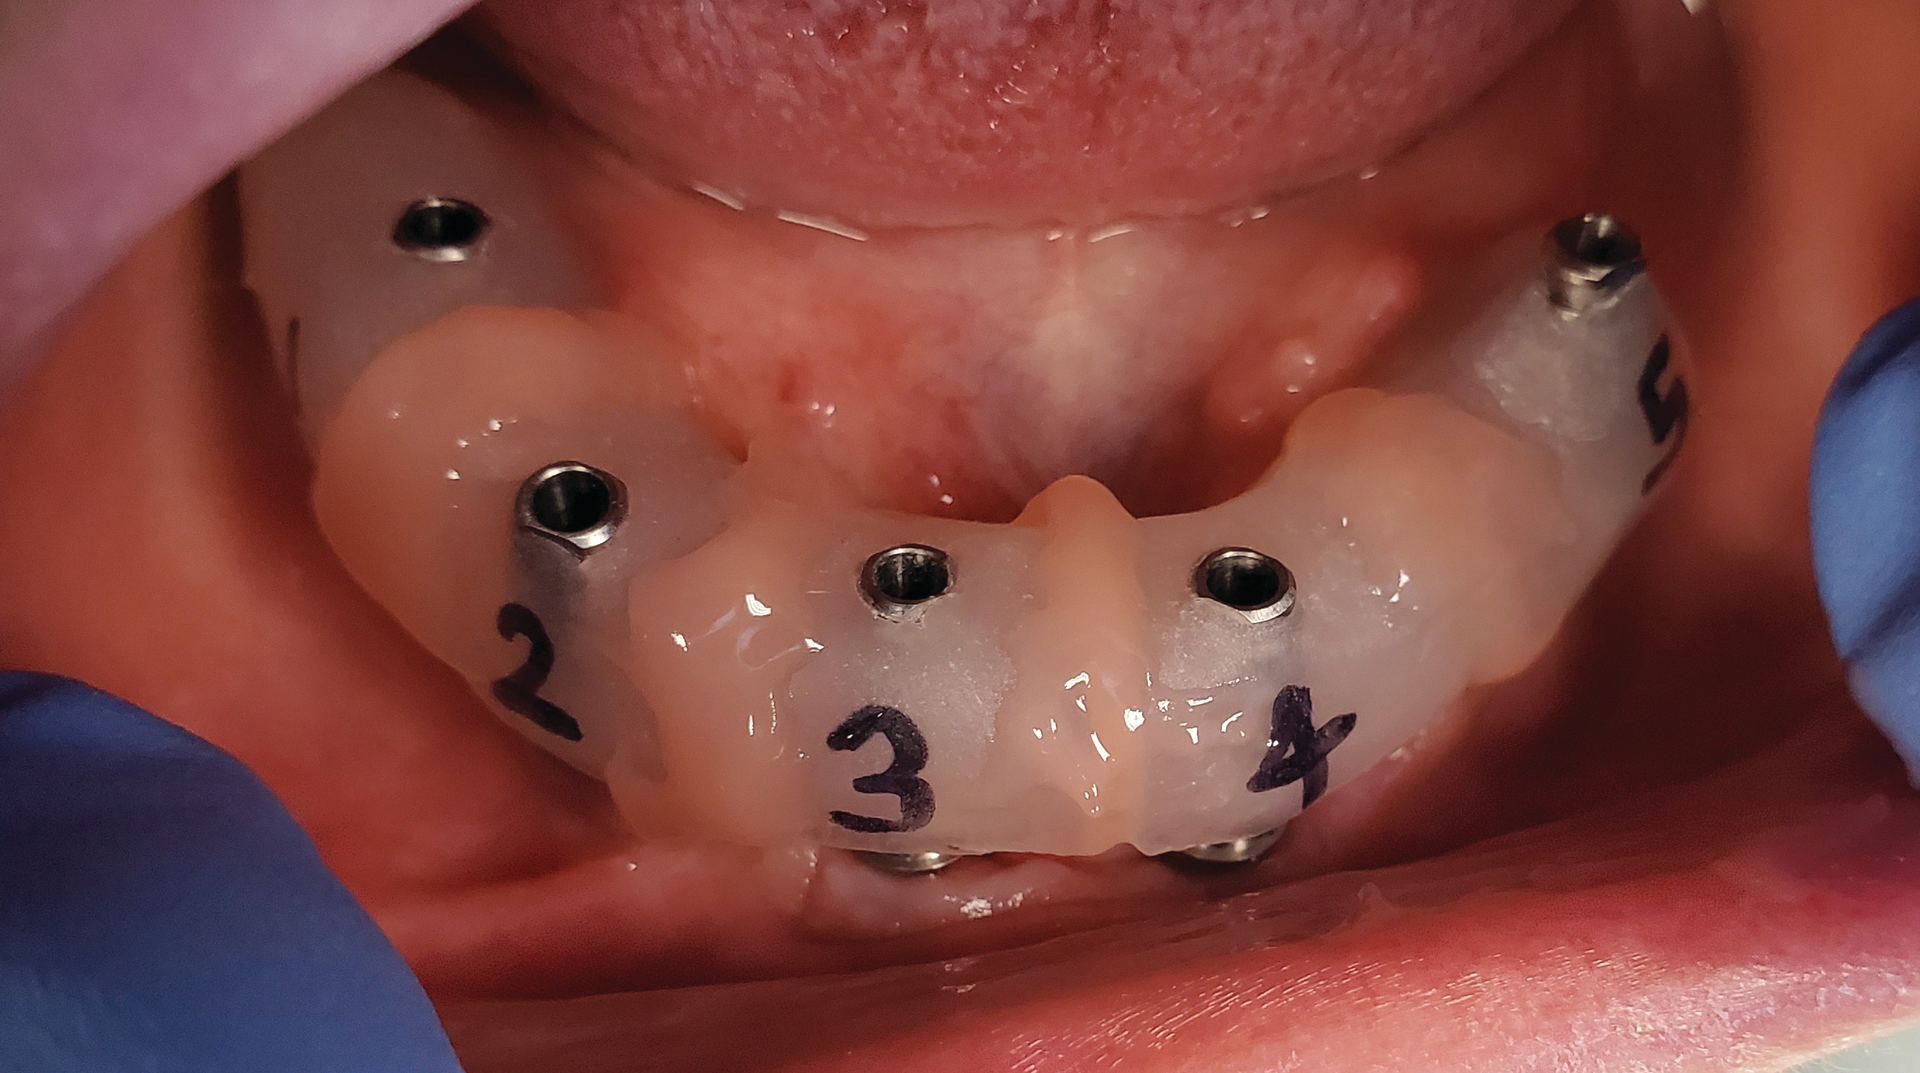

I seat the direct pickup copings hand-tight onto the multiunit abutment, syringe a light-body polyvinyl siloxane (PVS) around the coping, and then fill the MiraTray with medium or heavy-body PVS as well (figure 5). Seating the MiraTray is what makes it indispensable in the full-arch impression. The long screws of the direct pickup coping poke through the material on the tray, allowing easy access for the screw while keeping the material confined (figure 6). The tray is kept in place as the impression material sets up. Once it is ready, each of the copings must be unscrewed until the impression is released from the multiunits.

The impression should be checked for voids, inaccuracies, or distortion, but it has been my experience that this impression is very accurate; I have found no reason to lute the impression copings together with composite bridges. The impression can now be sent to the lab for mounting. I always have the lab return the master cast with the verification jigs.